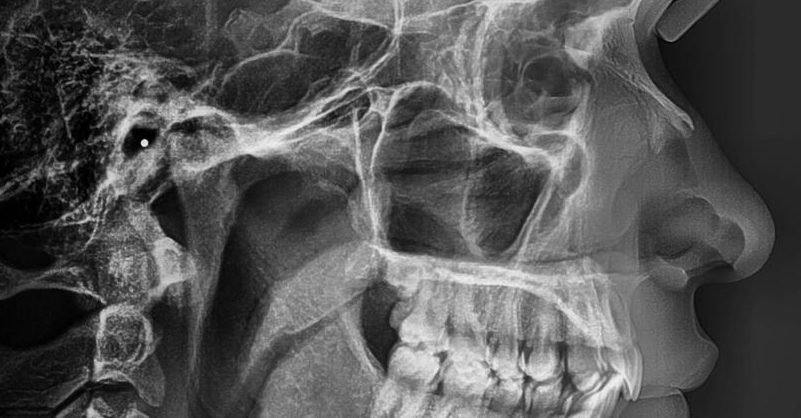

La radiografía lateral de cráneo permite un estudio del crecimiento facial del paciente y una valoración de las estructuras maxilares, mandibulares y sus relaciones con la base craneal.